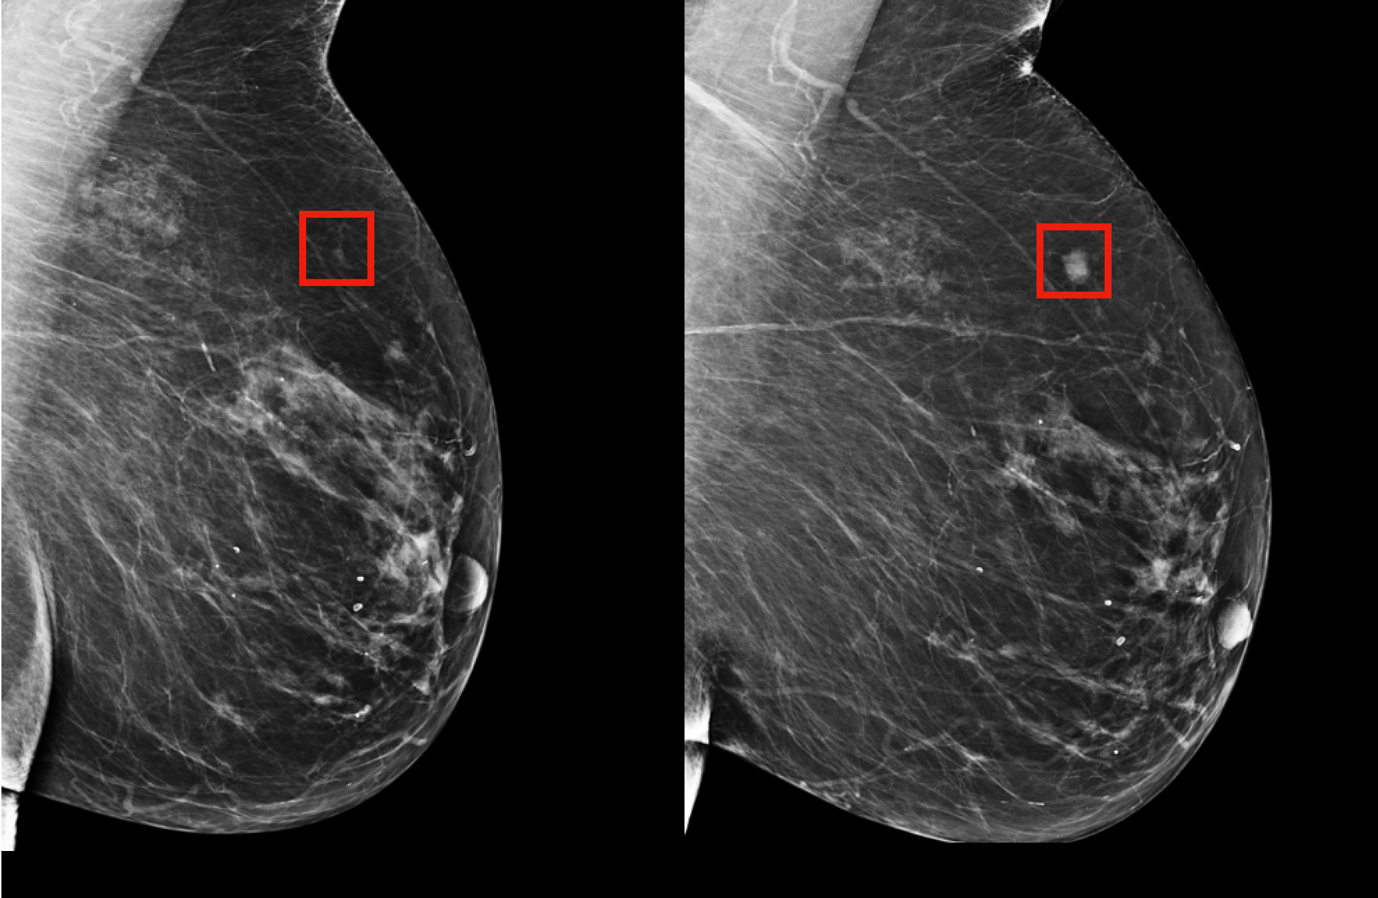

• Train deep learning models (e.g., convolutional neural networks) on the curated dataset to identify malignancies with high sensitivity and specificity.

• Incorporate explainable AI (XAI) techniques to provide interpretable outputs for clinicians, highlighting regions of interest in diagnostic images.